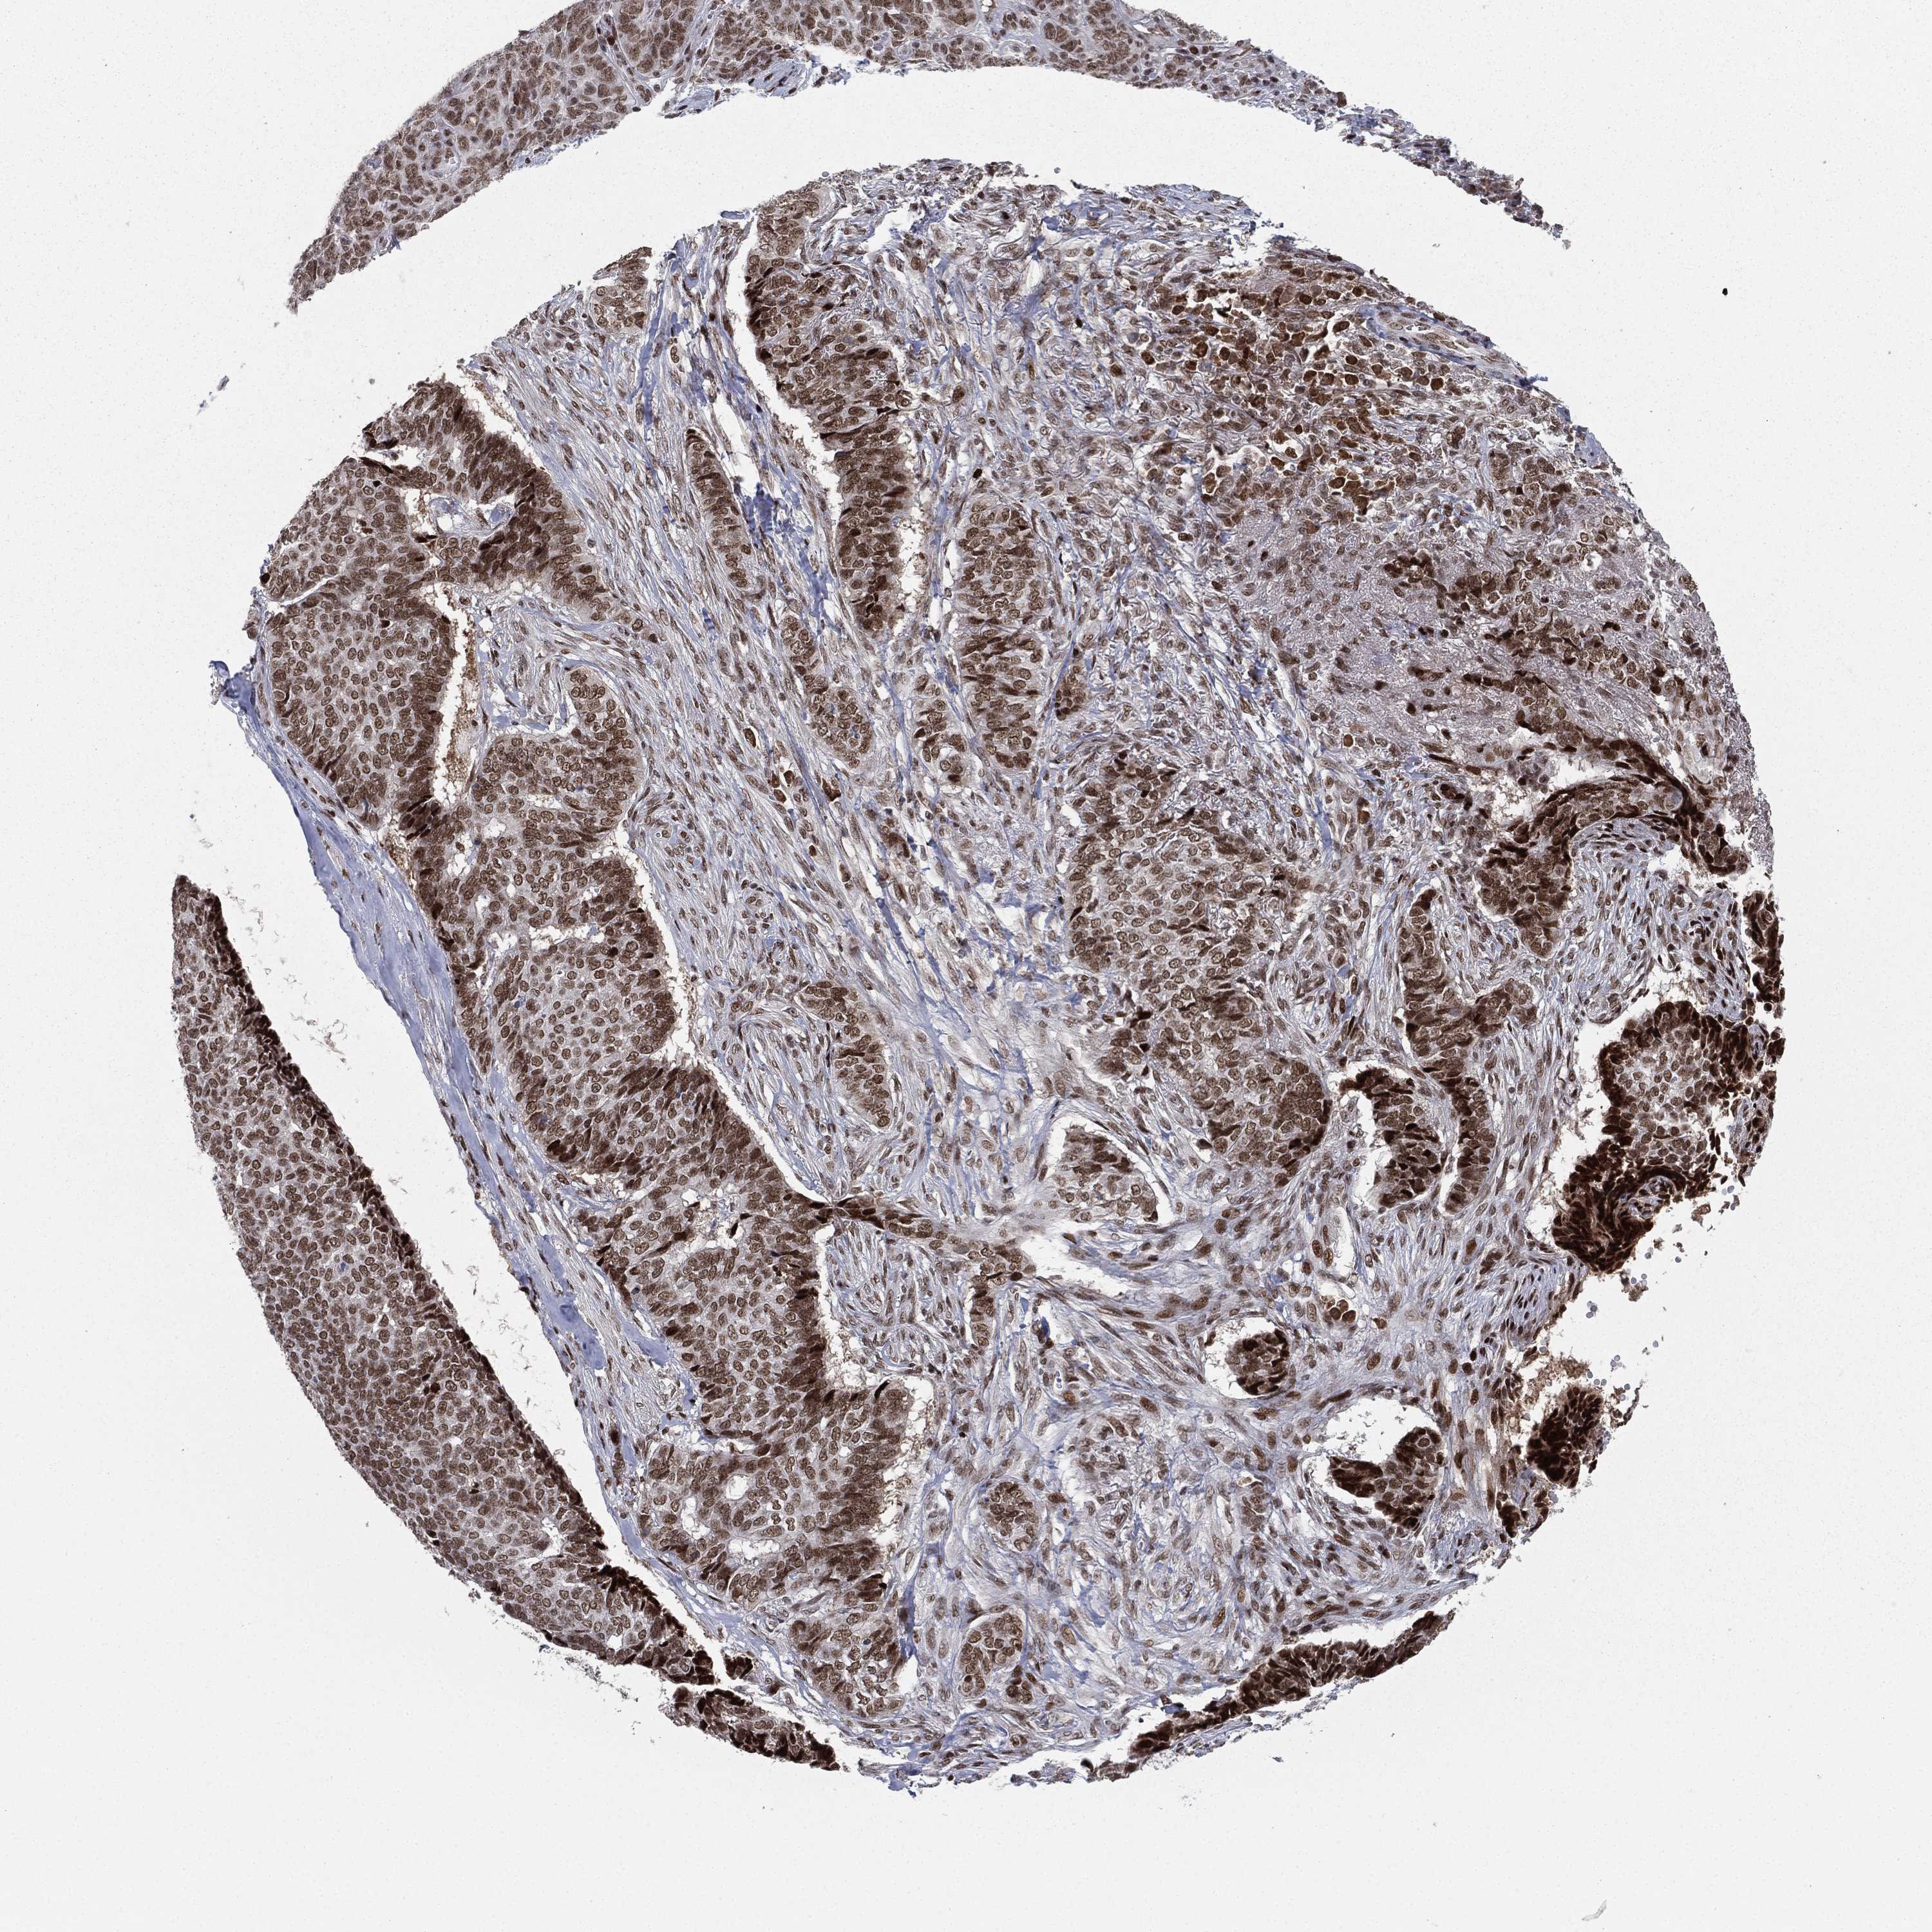

SKIN CANCER - Protein expressioni

A mouse-over function shows sample information and annotation data. Click on an image to view it in a full screen mode. Samples can be filtered based on level of antibody staining by selecting one or several of the following categories: high, medium, low and not detected. The assay and annotation is described here.

Antibody stainingi

Antibody staining in the annotated cell types in the current human tissue is reported as not detected, low, medium, or high, based on conventional immunohistochemistry profiling in selected tissues. This score is based on the combination of the staining intensity and fraction of stained cells.

Each image is clickable and will lead to virtual microscopy that enables deeper exploration of all samples and also displays staining intensity scores, fraction scores and subcellular localization as well as patient and tissue information for each sample.

Antibody HPA006714

Squamous cell carcinoma, NOS